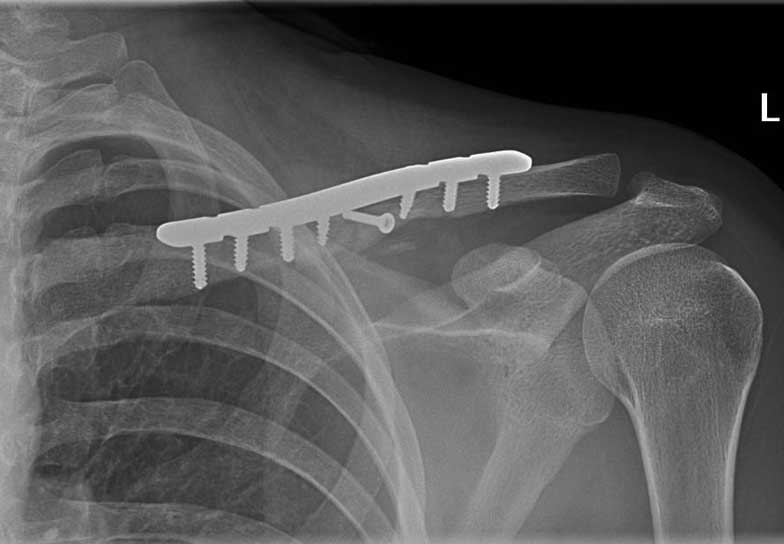

In my practice and what is generally becoming more accepted in the literature, is that most fractures of the clavicle that are displaced, angulated or overlapped are best treated with an operation. This operation can either be performed by realigning the bones in their original shape using a plate and screws on top of the bone or by using a pin that goes down the centre of the bone. Both of these techniques are successful and the decision generally comes down to the fracture pattern and the preference of the surgeon. The idea of the operation is to make the patient as comfortable as possible by making the fracture stable, and therefore allowing the patient to return to normal activities as soon as possible.

Generally all displaced fractures of the distal clavicle require surgery to increase the incidence of union. In my practice, the operation is performed by realigning the bones back to their original position using a plate and screws on top of the bone. The advantage of fixing them with a plate and screws generally means that you can start to move the arm a lot quicker and to also decrease the incidence of non-union.

The operation is performed with the patient under a general anaesthetic, in other words, completely asleep, and a small 3-4 cm incision is made under the collarbone, at the end of the shoulder. The fractured bone ends are exposed and put back into position using a plate and screws as shown below.

This fixation also needs reinforcement using special sutures around the plate and around the bone next to the clavicle called the coracoid process. The sutures are used to decrease the deforming forces from your shoulder muscles. In the majority of cases, in my hands, the operation is extremely successful resulting in the bone healing and the return of near normal function. In a small number of cases, the plate needs to be removed if it irritates the patient under the skin.